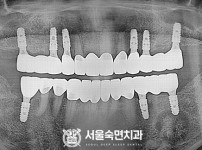

임플란트-전후사진3

임플란트-전후사진4